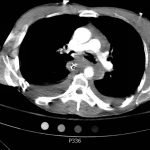

The initial chest x-ray showed an abnormal superior mediastinal contour (blue line), suggestive of a possible aortic injury. The CT angiogram showed extensive circumferential irregularity and outpouching of the distal aortic arch (red arrows) compatible with aortic transection. In addition, there was a circumferential intramural hematoma, which extended through the descending aorta to the proximal infrarenal abdominal aorta (green arrow). There was also an extensive surrounding mediastinal hematoma extending around the descending aorta and supraaortic branches (purple arrows).